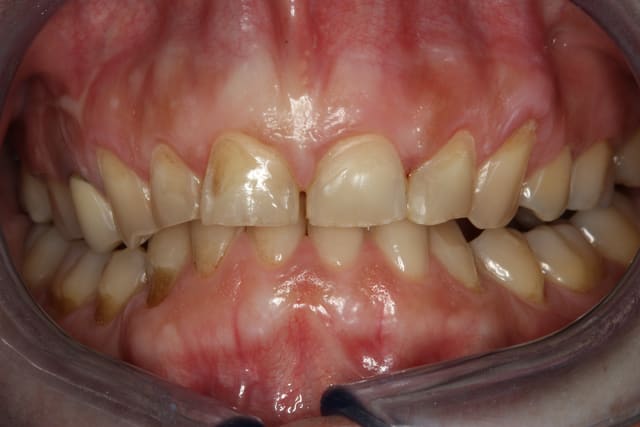

Bonjour,ma patiente présente des érosions des faces vestibulaires et est gênée esthétiquement car elles se colorent en quelques semaines après un détartrage et polissage. Elle me dit qu'elle serre les dents la nuit mais ne bruxe pas ( du moins son mari n'entend rien...). Au niveau alimentaire, il n'y a pas une consommation excessive de fruit, crudité, ni de boisson sucrée gazeuse. Ces érosions sont elles du au fait que la patiente serre les dents? Peut on envisager de les reconstituer avec des facettes ou est ce plutôt contre indiqué dans son cas? Merci pour vos conseils.

je suis quand même étonné qu'elle ne bruxe pas compte tenu des usures des bords libres antérieurs et des encoches en particulier 13 et facette abrasion versant V de 34.

en faisant bien attention à l'occlusion et aux trajets des contacts par rapport aux bords de collage des facettes, je pense qu'il n'y a pas de contre indication à la facette. prévoir peut être une gouttière de protection nocturne.

Le bandeau d'émail restant périphérique est caractéristique d'une érosion chimique...

Pas toujours, l'émail saute où s’exercent les contraintes, si c'est au milieu de la face vestibulaire (pour des incisives) il en restera en dessous.

Dans ton cas, sur les photos il semble y avoir un recouvrement incisif excessif, d'où surpression en propulsion, il faudrait aussi voir si elles ne sont pas (11 et 21, en fait le bloc incisivo-canin) trop lingualées, cela pourrait expliquer les deux fêlures verticales de l'émail.

La facette d'usure sur la 43 très marquée par rapport aux collatérales postr... le bloc antr mandibulaire appuie fort (c'est un contraint?).

Si tu fais des facettes tu risques d'avoir les même fêlures en vestibulaire ou pire, il faudrait tester ou "libérer" la mandibule, si quelqu'un a une idée?